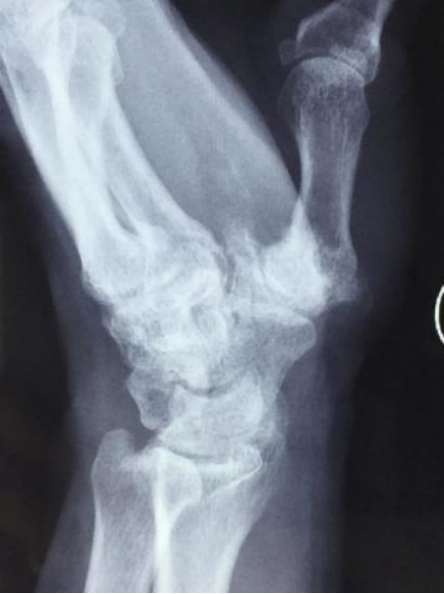

第一腕掌关节骨性关节炎X线影像学改变

X线表现:早期可无明显变化,随病情进展,出现典型的骨关节炎表现,关节间隙不对称性狭窄,软骨下骨硬化、囊性变,骨赘形成、骨端相对增大,以及第一腕掌关节的桡背侧半脱位。

第一腕掌关节骨性关节炎Ⅲ期影像学改变